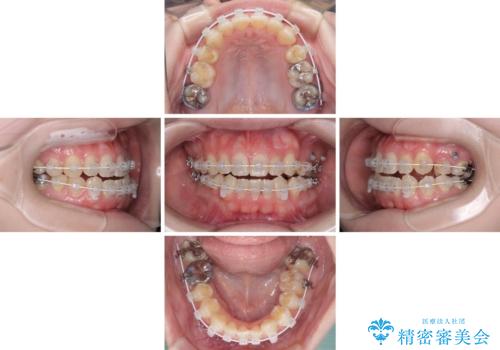

八重歯と前歯の欠損と骨格のズレ 目立たないワイヤー矯正

- 左上の八重歯と前歯のデコボコを気にして来院された患者様です。

下顎が左側にズレており、下顎前歯は1歯欠損していたため、左上小臼歯1本を抜歯し、ワイヤー装置にて矯正治療を行うこととしました。

骨格のズレと歯の欠損があったため、仕上がりの調整に時間がかかると思いましたが、舌突出癖の改善や顎間ゴムの装着をしっかりと行ってくださったので、速やかに治療を終えることができました。